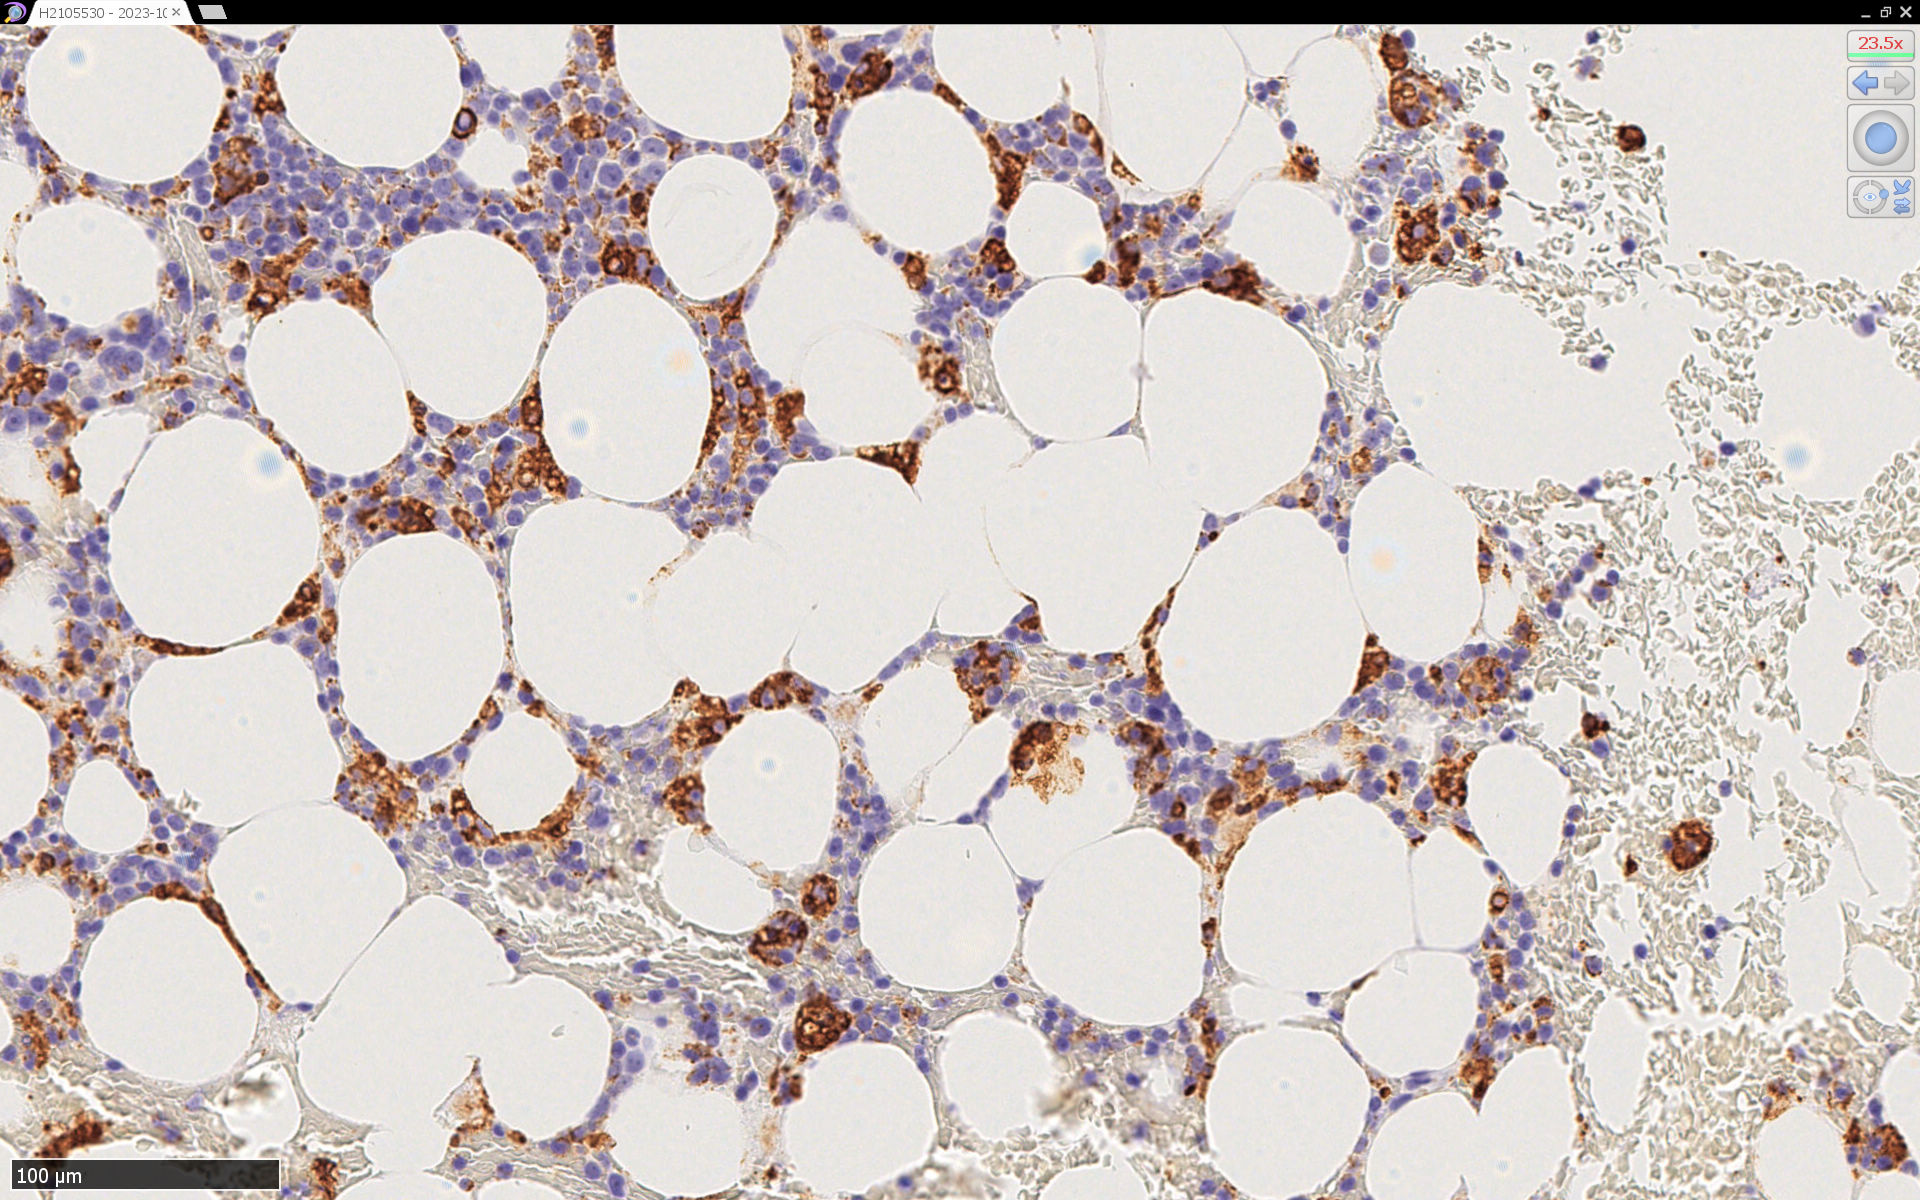

症例の報告, 骨髄病理所見--IWT case

CD68(KP-1)

CD68(PG-M1)